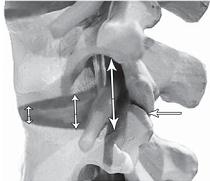

Фото № 12

На фото № 12 макета позвоночника наблюдается перерастяжение дугоотростчатого сустава вследствие вытяжения, расширение фораминального отверстия, а также растяжение задних отделов фиброзного кольца межпозвонкового диска и сближение вентральных (передних) отделов тел позвонков. Это приводит межпозвонковый диск в клиновидное состояние, что способствует выталкиванию содержимого межпозвонкового диска из передних его отделов в задние.